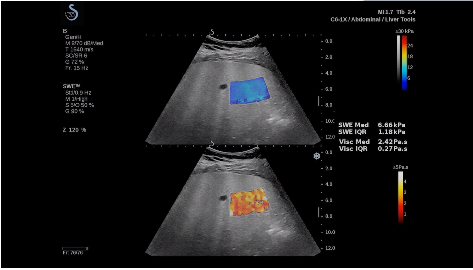

法國聲科影像(SuperSonic Imagine,SSI. Euroniex:FR0010526814)近日發(fā)表公告,宣布其研發(fā)的新一代“極速”超聲成像平臺(UltraFast Imaging),首次實(shí)現(xiàn)了肝臟的多項(xiàng)超聲定量評估新指標(biāo)同步檢測,包括:Att PLUS,SSp PLUS和Vi PLUS等,基本涵蓋肝臟相關(guān)病理變化指征的如纖維化、脂肪變、炎癥等。據(jù)悉,此多項(xiàng)新技術(shù)新將搭載于新Aixplorer系列E超系統(tǒng)。

E超相關(guān)技術(shù)已被多項(xiàng)多中心大樣本研究證實(shí)對于肝纖維化無創(chuàng)評估有重要意義,同時(shí)也可全面應(yīng)用于乳腺、甲狀腺、肝臟、前列腺、肌骨、婦科等全身各組織器官的定量評估和鑒別診斷。在慢性肝臟方面,聲科E超的肝臟相關(guān)定量診斷技術(shù)集,于2018年獲得美國FDA認(rèn)證,成為FDA歷史上首次獲批的單病種超聲全面定量解決方案。

E超是在原有B超、彩超(彩色多普勒CDFI)基礎(chǔ)上研發(fā)成功的新一代超聲剪切波彈性成像系統(tǒng),是一種能夠全面應(yīng)用于表淺組織、腹部臟器,血管等方面的組織彈性成像技術(shù)。根據(jù)組織硬度彈性值的不同,有效鑒別實(shí)性腫瘤的良惡性。對于惡性病變的診斷具有較高的特異性和敏感性,尤其對于甲狀腺、乳腺、前列腺等小器官,能夠完成常規(guī)超聲不能完成的組織定量分析,可以實(shí)時(shí)、全幅、全定量獲得組織彈性(硬度)信息,為鑒別腫瘤的良惡性提供客觀、量化的診斷依據(jù)。